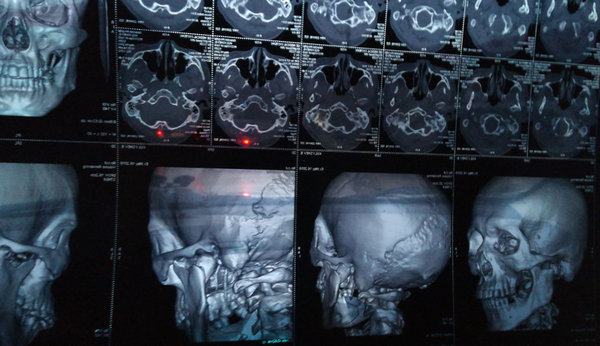

Полгода назад получил травму — двойной перелом нижней челюсти со смещением. Поставили две пластины, удалили осколок кости примерно 3 см, зуб в области перелома не удалили.

В данный момент наблюдается потемнение десны в месте перелома и выделение гноя. В моем городе нет ЧЛХ. Стоматологические клиники отвечают неоднозначно. Одни говорят, что необходимо просто удалить зуб, другие отвечают, что необходима операция (повторное шинирование, удаление зуба и чистка, с возможной переустановкой пластины).

Зуб из линии перелома необходимо удалить, т.к. он служит источником инфекции, отсюда и рецидив. Также провести ревизию воспалительного очага.